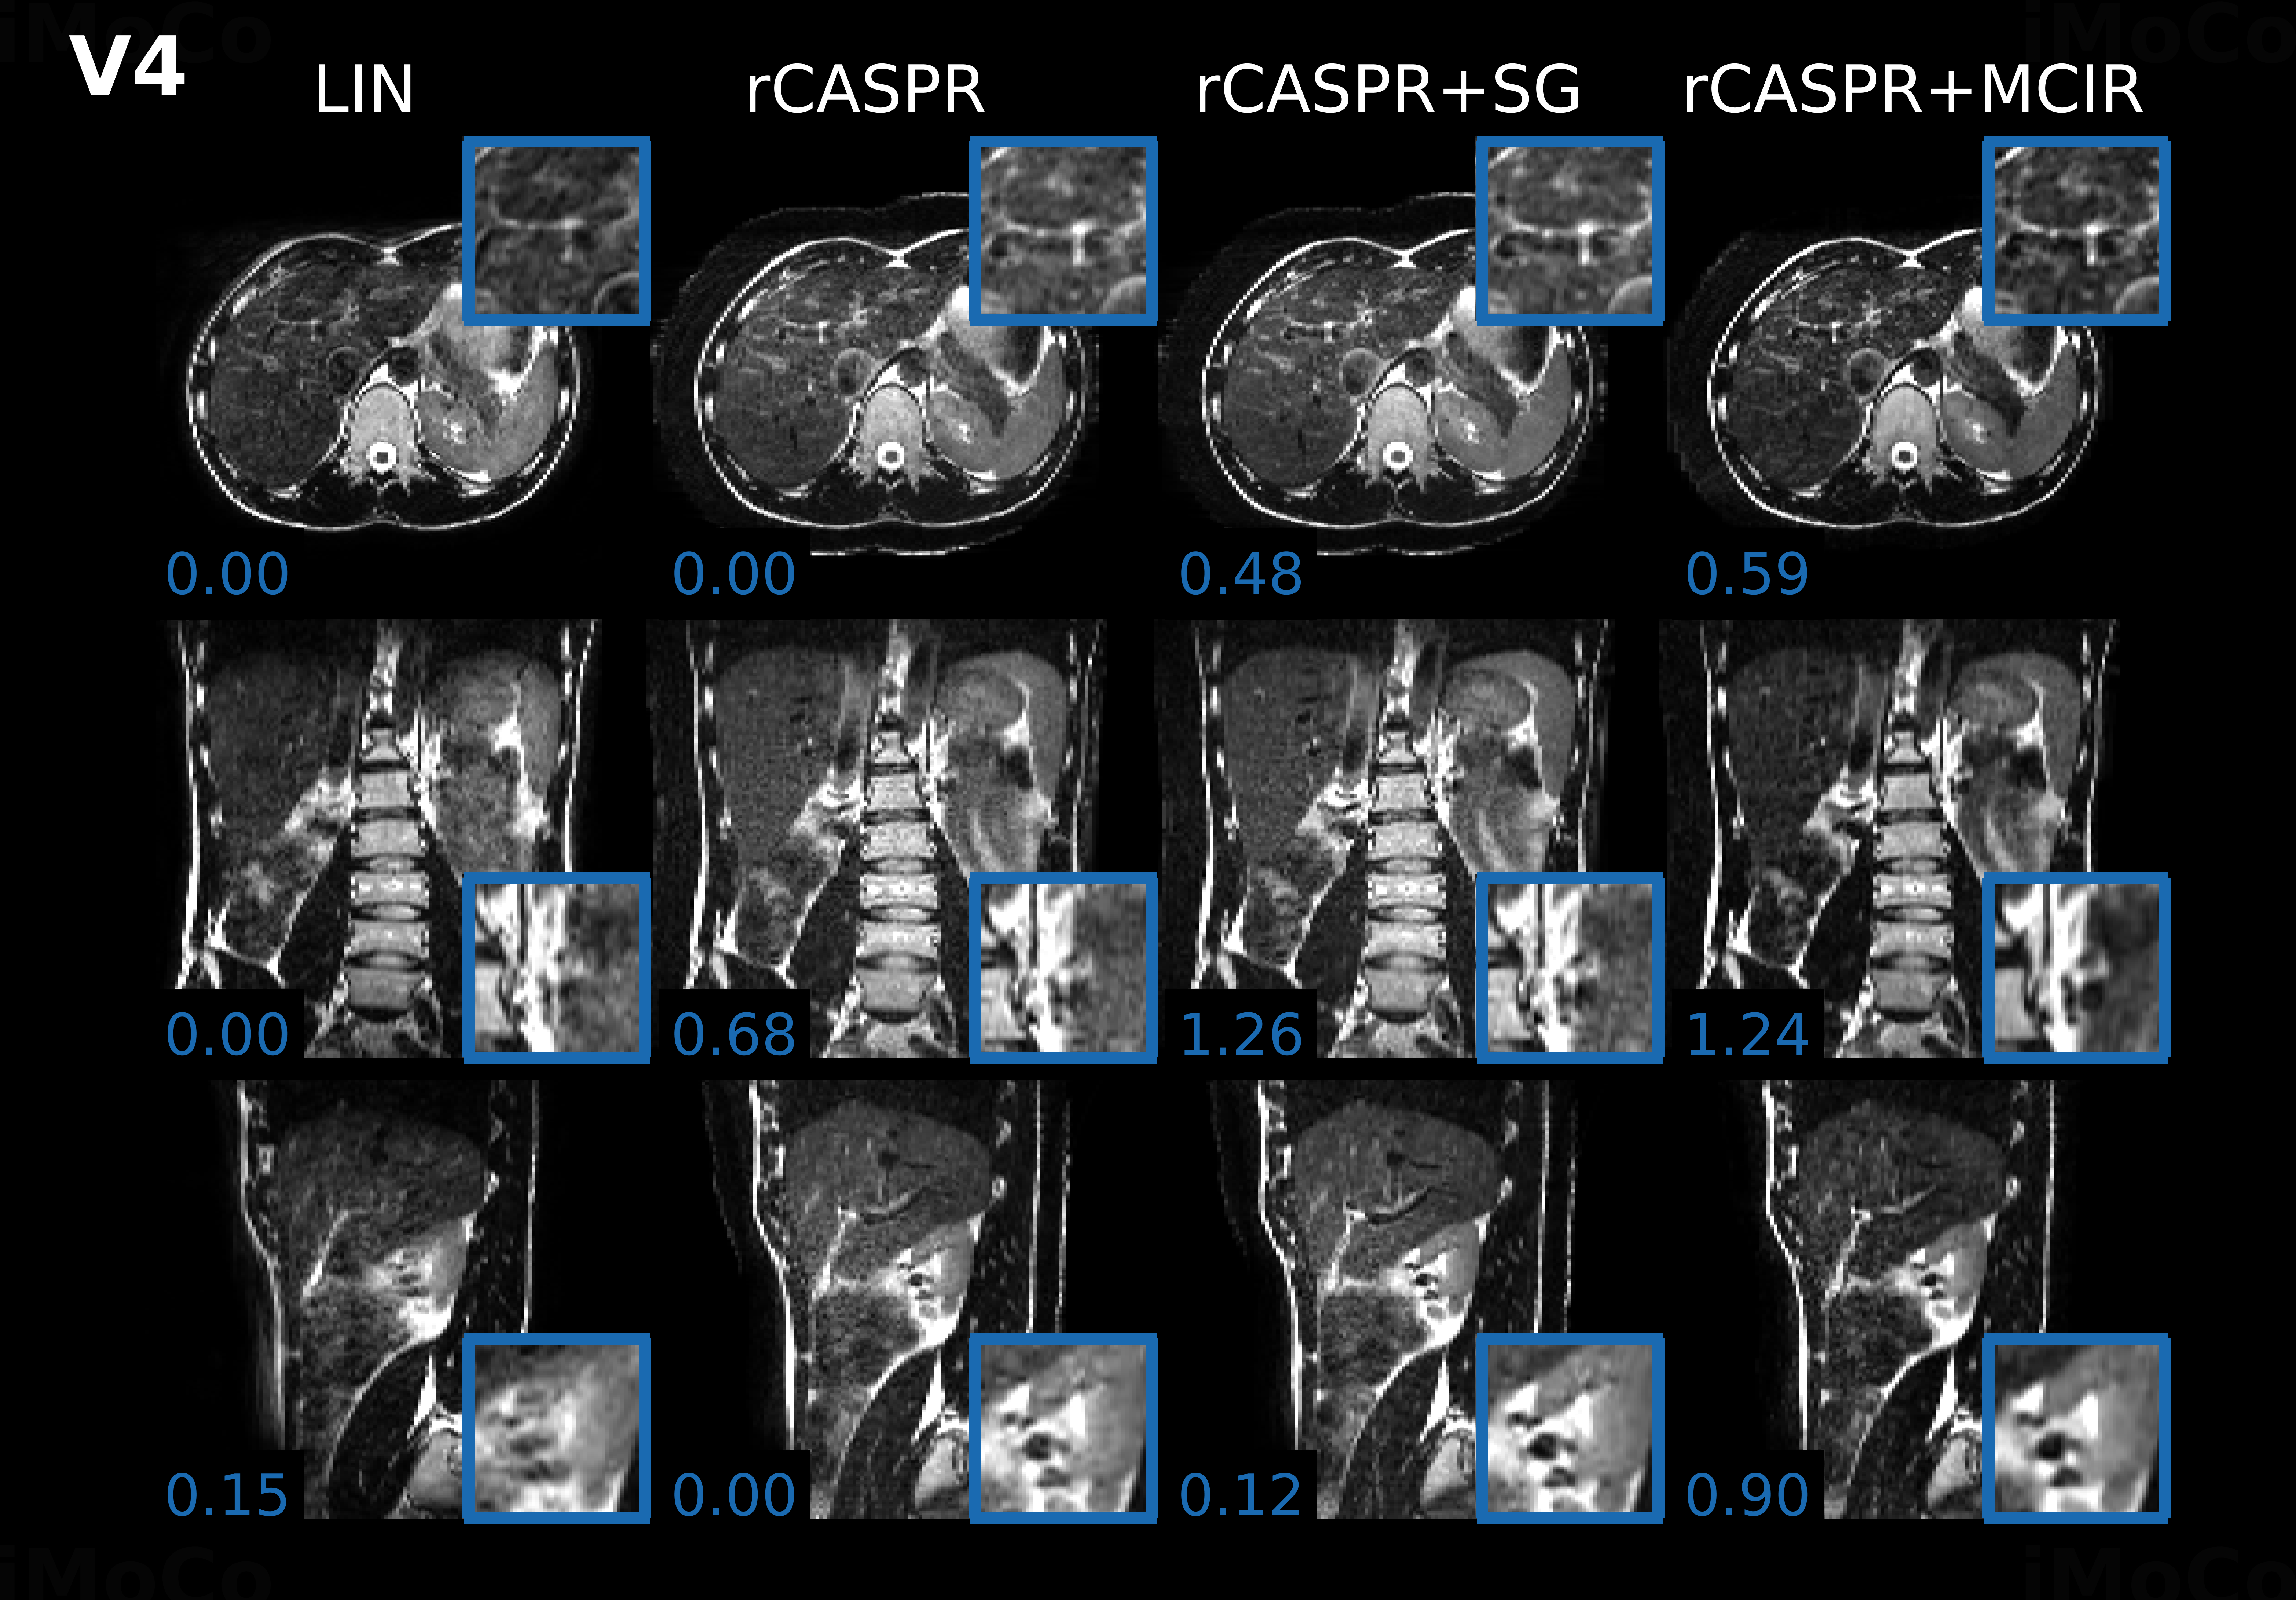

Figure 6 shows the respiratory-correlated 4D-MRI reconstructions for four of the volunteers with the optimal hyperparameters described in the previous paragraph. The figure also shows the |D​V​F|đ·đ‘‰đč|DVF| that describes the transformation between the exhale and inhale respiratory phase. Most volunteers show maximum displacement at the top of the liver larger than 1 cm, only volunteer 2 shows considerably smaller motion. As expected, almost no motion is visible in the static regions of the image (e.g. spine), indicating that residual aliasing artefacts do not affect the motion estimation.

Refer to caption

Figure 6: Respiratory correlated low-resolution 4D image reconstructions with the corresponding deformation vector fields. The different volunteers are indicated with ”Vx”, where ”x” refers to the volunteer index. The two grayscale images show the image reconstructed at the inhale and exhale position and the color coded images show the |D​V​F|đ·đ‘‰đč|DVF| that describes the motion between these respiratory positions. Note that all volunteers show peak motion ≈\approx 1 cm with the exception of volunteer 2. The blue dashed line indicates the position of the liver/spleen in the exhale phase and aids in the visualization for the inhale phase. Acronyms: DVF = deformation vector field.